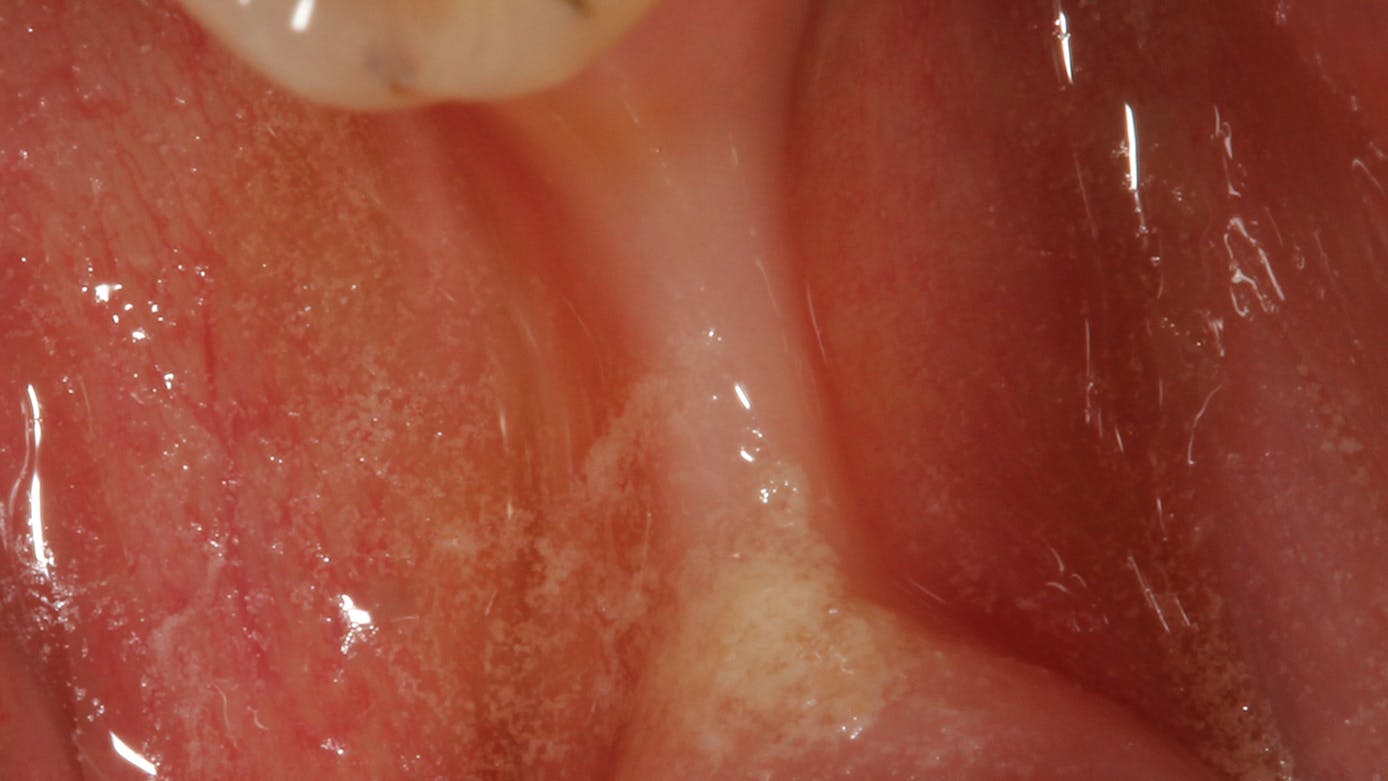

• site development to increase hard and soft tissue for pontic sites in fixed bridge prosthetics (figures 9–14);• correcting bone defects impinging upon anatomical structures after tooth extraction, such as oroantral communication (figure 18); and

• preserving tissue structure for subsequent dental implant therapy.Decision matrix